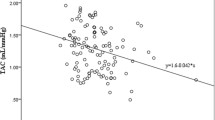

Table 4 shows the correlation between beat-to-beat BPV measures and PWV and the relation between the mean level of BP and PWV in each phase of the CPT. The results indicate that mean levels of BP were significantly correlated with PWV in all three phases (r = 0.26–0.34, P < 0.05). In addition, the ARV and the SV of DBPV in the cold stimulus phase also showed significant correlation with PWV (r = 0.22–0.25, P < 0.05). In addition, the scatter plots in Fig. 1 further confirm the linear correlation between the ARV and the SV of DBPV in the cold stimulus phase and PWV.

In the present experiments, an important finding was that the ARV and SV of beat-to-beat DBPV in the cold stimulus phase showed significant correlations with PWV, indicating that both the mean level and variability of beat-to-beat BP have a strong influence on arterial stiffness in the pre-hypertension stage. It has been suggested that ARV is a more appropriate measure of variability and a more useful predictor of cardiovascular outcome [37]. ARV can also be usefully applied to visit-to-visit measurements. Therefore, ARV provides a computationally simple way of estimating variation about a trend. SV will be highly correlated with ARV, tending to be larger in absolute value and influenced to a greater extent by large discrepancies between successive measurements. These two parameters very accurately reflect the variability of DBP. DBP mainly reflects the magnitude of the peripheral resistance. High peripheral resistance is a major cause of high BP.

Several studies have been conducted with the aim of disentangling the precise contribution of humoral, neural, and environmental factors to BPV [39–41]. In previous studies, Fang-Fei Wei et al. reported that beat-to-beat BPV was used to evaluate target organ damage [6]. This study mainly explained that short BPV, such as beat-to-beat recordings, even as short as 10 min, was associated with LVMI independent of level. In another study, they found a positive correlation between systolic and diastolic BPV and PWV in hypertensive patients [42]. During the experiment, they measured 24-hour BPV using SD and CV. Similarly, we come to the conclusion that the ARV and SV of DBPV in the CPT are also related to PWV (r = 0.22–0.25, P < 0.05).